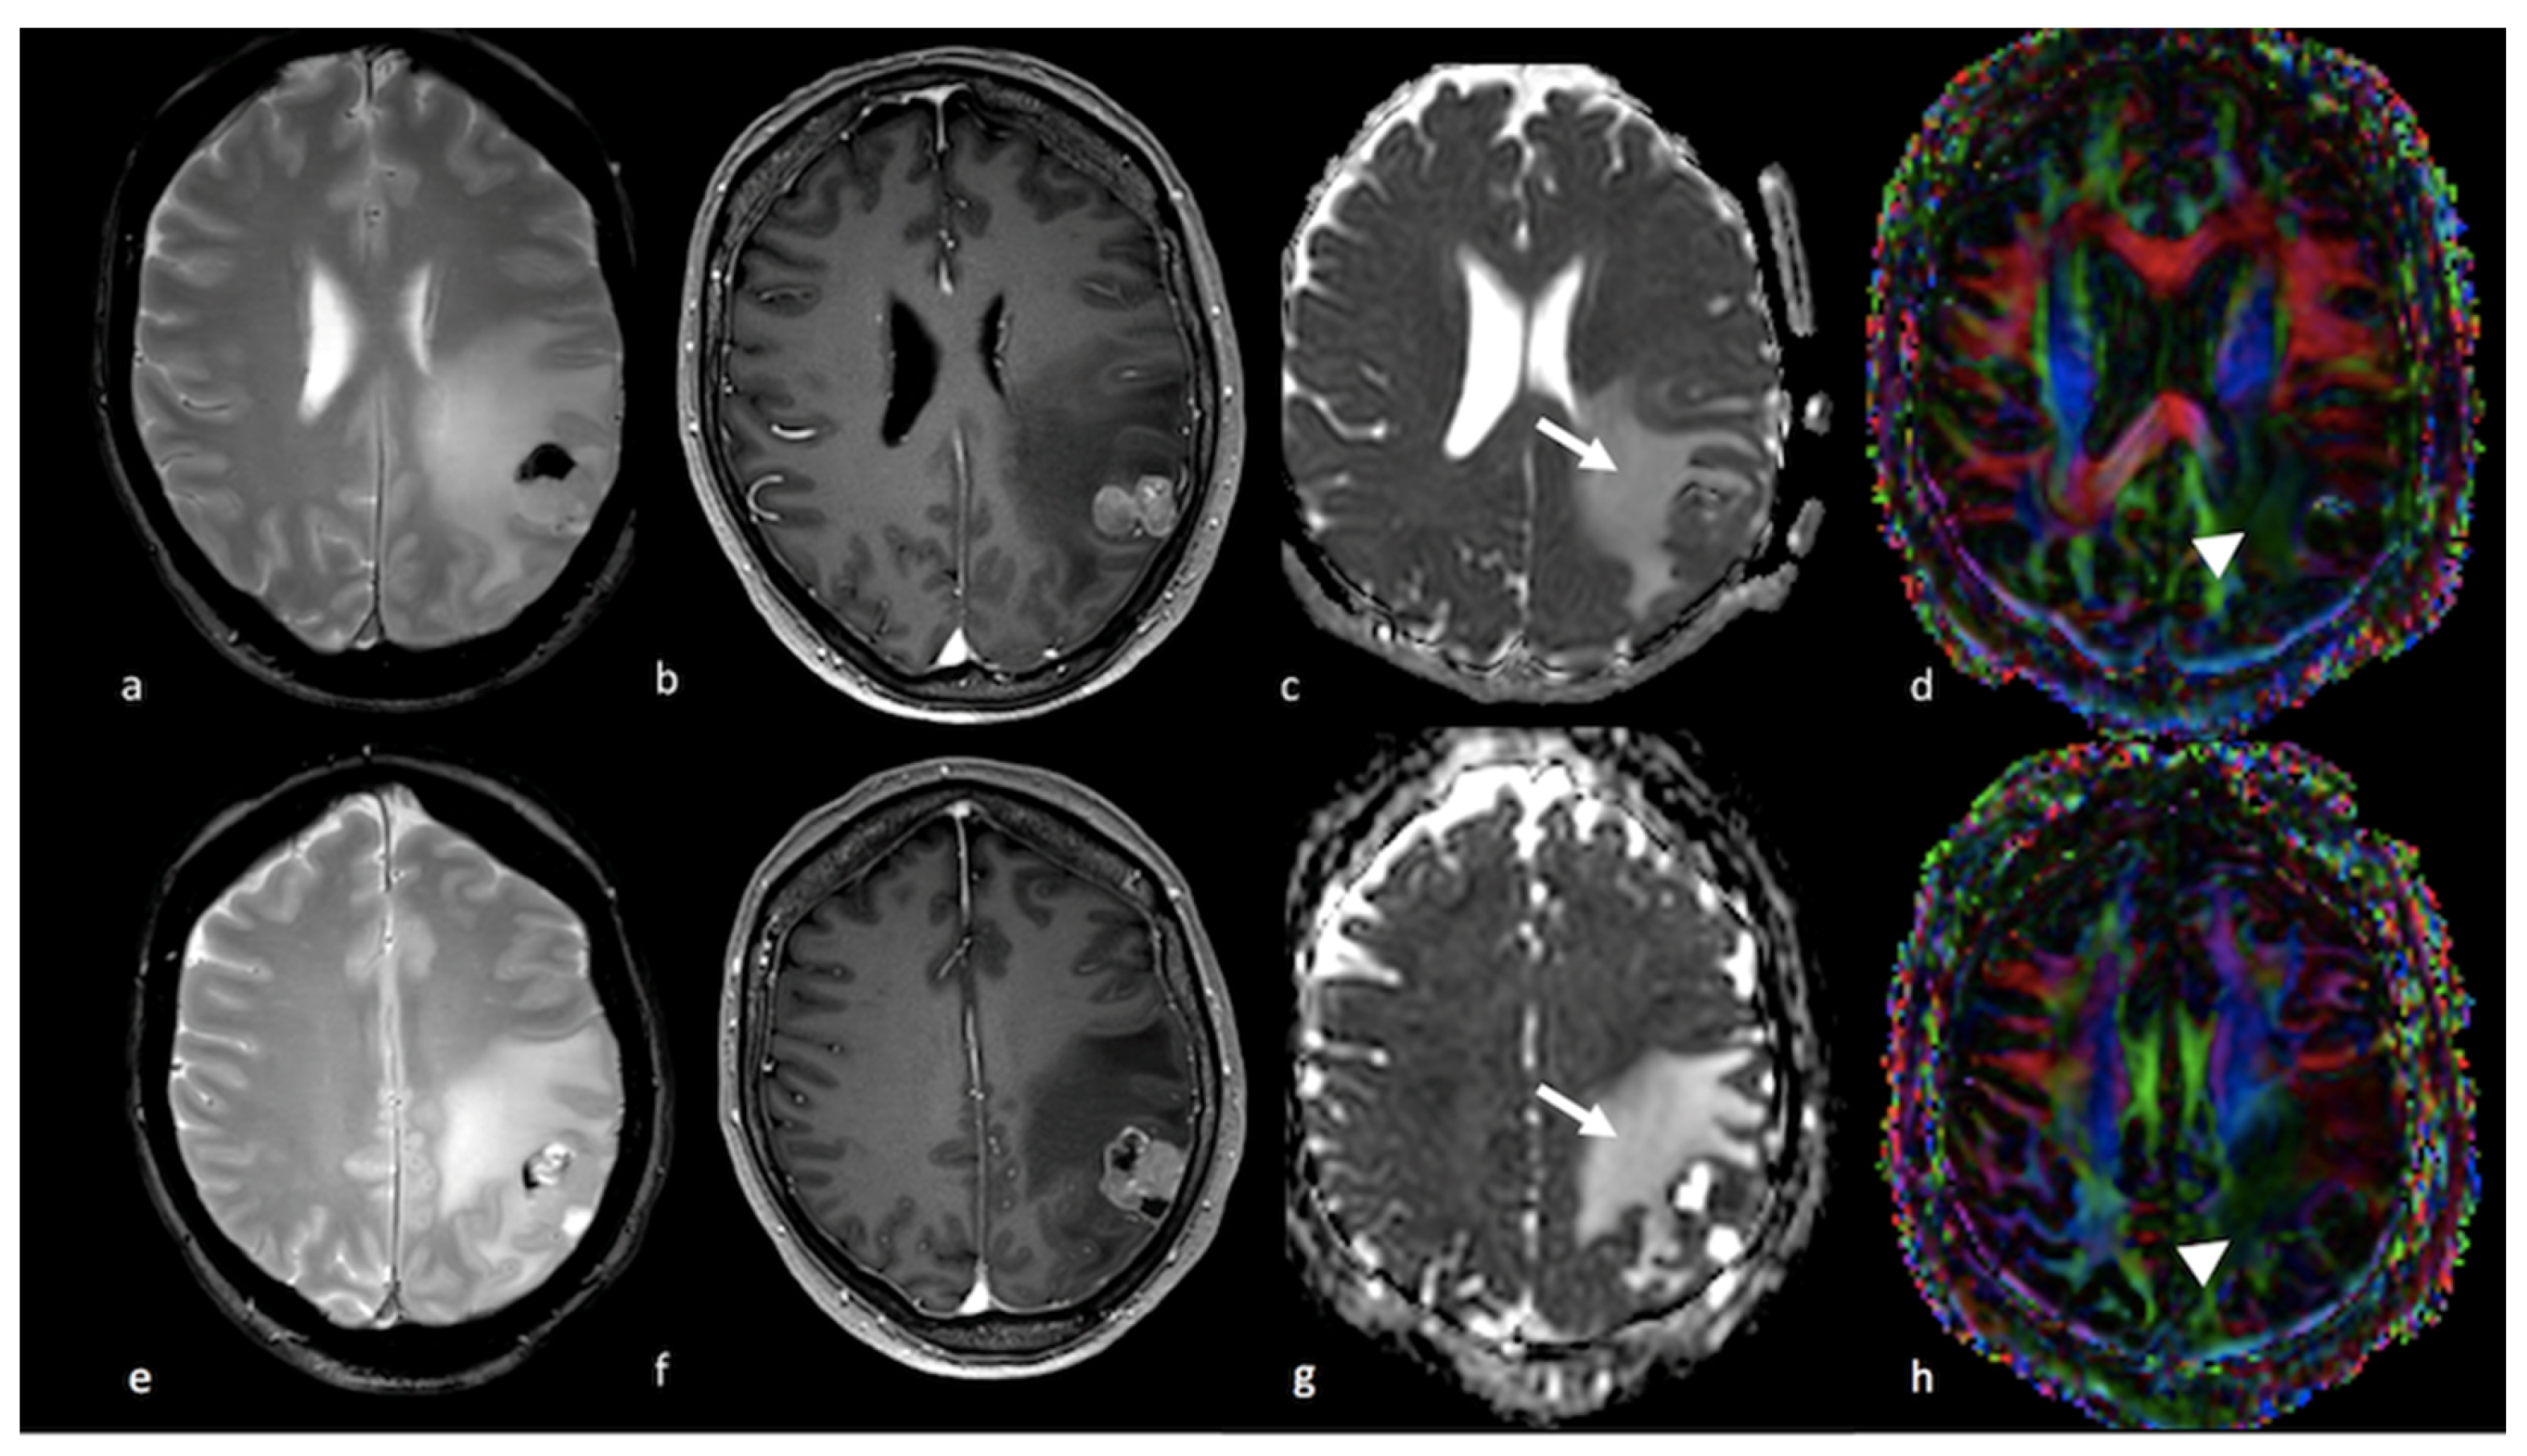

3.2.2. Diffusion Tensor Imaging (DTI)

- Lee, E.J.; Ahn, K.J.; Lee, E.K.; Lee, Y.S.; Kim, D.B. Potential role of advanced MRI techniques for the peritumoural region in differentiating glioblastoma multiforme and solitary metastatic lesions. Clin. Radiol. 2013, 68, e689–e697. [Google Scholar] [CrossRef]

- Byrnes, T.J.; Barrick, T.R.; Bell, B.A.; Clark, C.A. Diffusion tensor imaging discriminates between glioblastoma and cerebral metastases in vivo. NMR Biomed. 2011, 24, 54–60. [Google Scholar] [CrossRef] [PubMed]

- Sternberg, E.J.; Lipton, M.L.; Burns, J. Utility of diffusion tensor imaging in evaluation of the peritumoral region in patients with primary and metastatic brain tumors. AJNR Am. J. Neuroradiol. 2014, 35, 439–444. [Google Scholar] [CrossRef]

- Doishita, S.; Sakamoto, S.; Yoneda, T.; Uda, T.; Tsukamoto, T.; Yamada, E.; Yoneyama, M.; Kimura, D.; Katayama, Y.; Tatekawa, H.; et al. Differentiation of Brain Metastases and Gliomas Based on Color Map of Phase Difference Enhanced Imaging. Front. Neurol. 2018, 9, 788. [Google Scholar] [CrossRef] [PubMed]